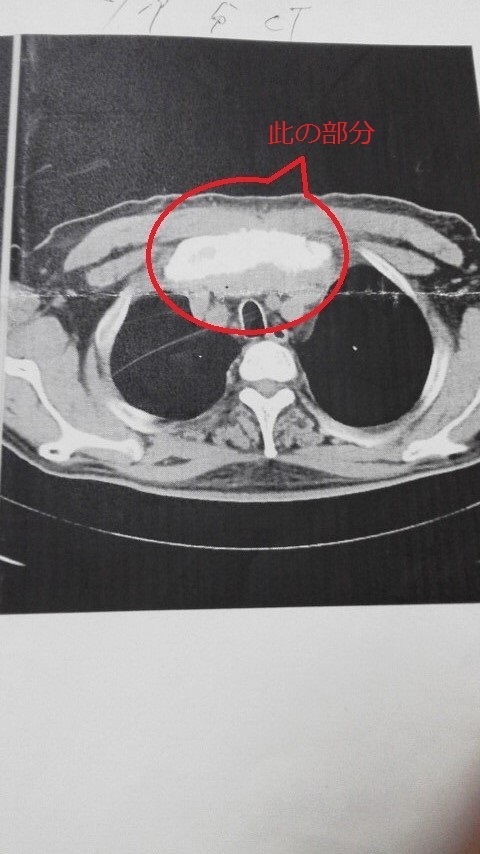

マダコも月に一度の脳神経外科。頭の方は何ともなくて、頻尿を訴えると腹部CTを撮られ、膀胱炎・前立腺肥大・胆嚢(母は胆管ガンで死去)に白い影が……などと脅されました。薬を増やされて、一週間で良くならない場合は云々……

胆嚢の白い影て少し気に成りますね、

自分も降圧剤飲んでます...膀胱炎・頻尿その他モロモロ!!!

マァ〜同じですねでも....胆嚢診察して置いて下さい””誤診も有りますので、

自分の胸の腫瘍も悪性腫瘍の診断でしたが...誤診でしたでも3ヶ月に一度検診は受けてますので、

MRでの自分の胸部腫瘍と正常な人の胸部です...可なり自分のは大きいですョ、

【追伸】

降圧剤による、腎臓・肝臓などへの影響可なり有ります自分の腎不全も原因不明との診断ですが看護婦さんとの話では薬の影響カナ”””